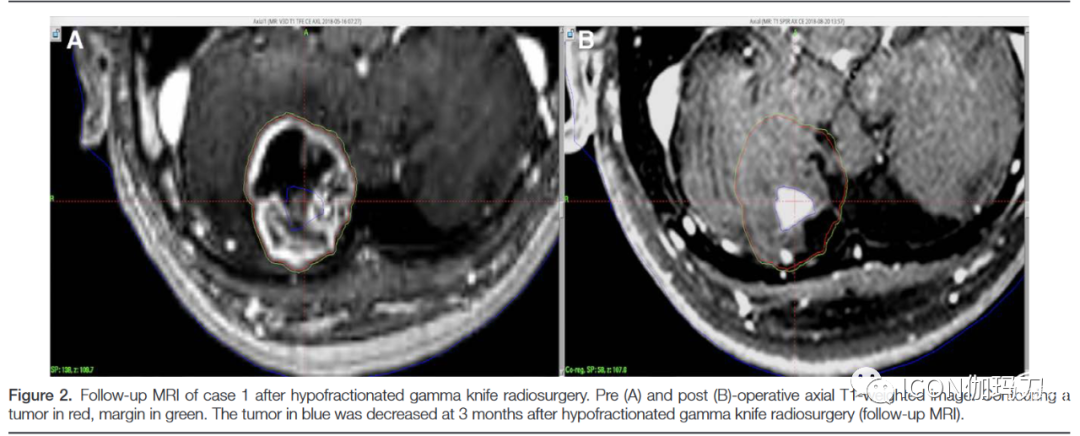

在规划GKRS时,肿瘤边缘比现有肿瘤切缘大0.5 mm,如图2所示。我们使用MATLAB (R2018a版本,MathWorks, USA)从LQ模型简单计算处方剂量(50%边缘)。几乎所有BM均遵循α/β = 10。根据LQ模型方程(BED = nD [1 + [D/ (α/β]]),根据图3中分割次数选择处方剂量。